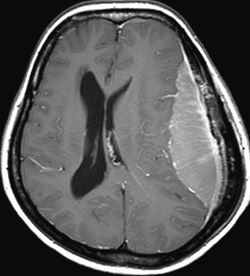

hidrosefali adı verilen ve kabaca beyin boşluklarındaki sıvı miktarının artışının,